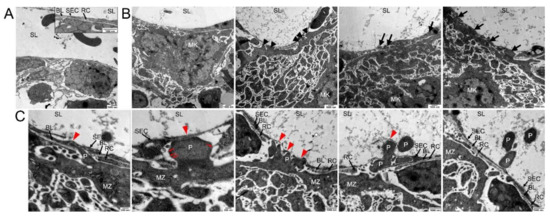

3.2. Ultrastructure of Megakaryocyte Protrusions during the Transendothelial Passage